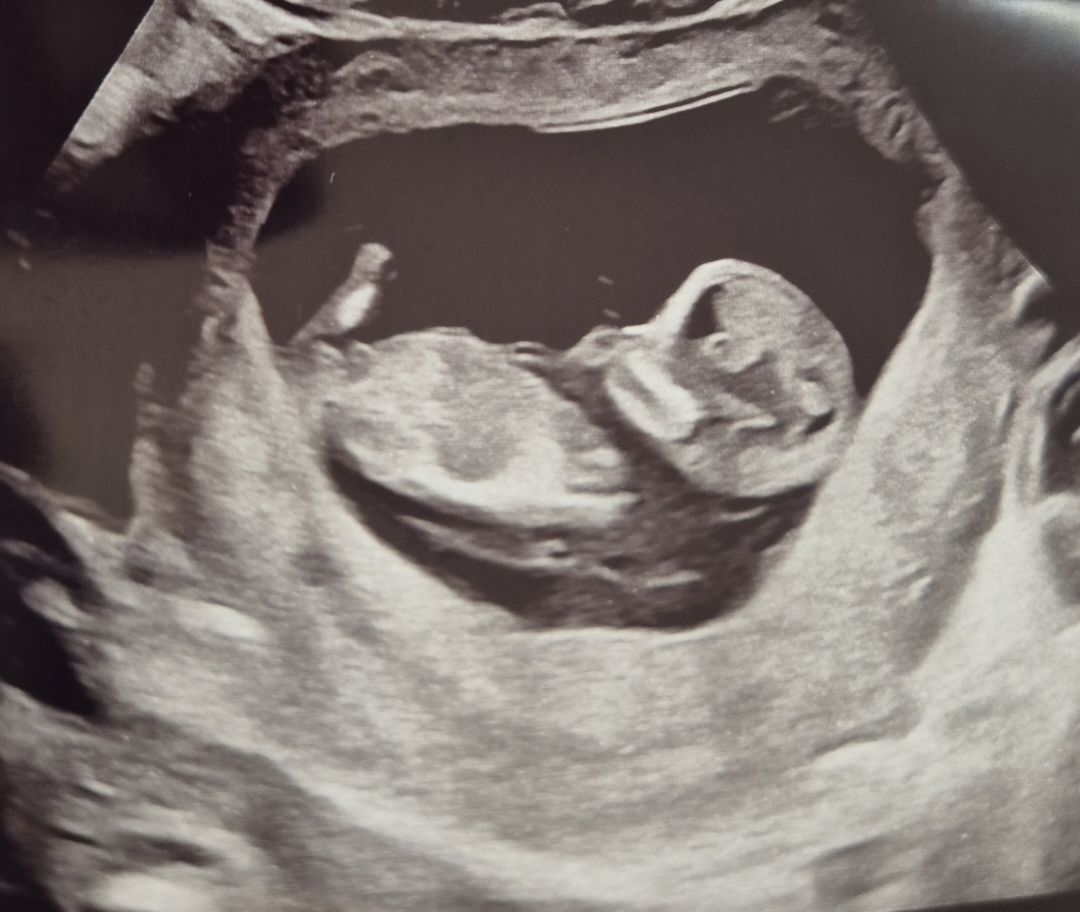

저거 꼬추 아니겠지요...?ㅋㅋㅋ

11주 5일차에 기형아 검사한다고 병원가서 초음파 사진을 받았는데 성별은 1달 후에 알수있다고 하셨거든요!! 지금은 모른다고! 근데 배꼽 밑에 뭐가 튀어나와있는데 저게 꼬추 아닌가.. 지금 시기에는 저렇게 보일 리가 없나 궁금해서 여쭈어봅니다 하핳